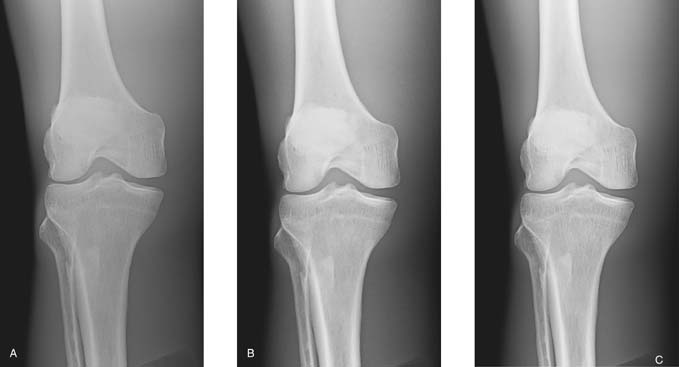

The brightness of a digital image can be altered during image processing; hence, information about the exposure to the IR is important. Manufacturers of each type of digital system specify the expected range of x-ray exposure sufficient to produce a quality image. A numerical value (exposure indicator) is displayed on the processed image to indicate the level of x-ray exposure received (incident exposure) on the digital IR. It is important for the radiographer to consider the indicated value because exposure errors, as previously stated, affect the quality of the digital image and the radiation dose to the patient. Exposure errors are not obvious by simply looking at the digital image because the digital data are normalized to provide images with diagnostic brightness levels (Fig. 6-4). Most manufacturers of digital IRs suggest a range for the exposure indicator on the basis of the radiographic procedure. If the exposure indicator value falls outside this range, exposure to the digital IR, image quality, and patient exposure could be affected.

FIG. 6-4 Exposure errors can be computer adjusted to maintain image brightness. A, Image created with sufficient mAs. B, Image created with insufficient mAs, resulting in increased quantum noise visible. C, Image created with excessive mAs, resulting in decreased quantum noise visible. The exposure indicator value reflected the exposure errors to the IR for images B and C. (From Johnston JN, Fauber TL: Essentials of Radiographic Physics and Imaging, ed 3, St. Louis, 2020, Mosby.)

A diagnostic-quality image (Fig. 6-7A) was produced using 70 kVp at 2 mAs. Fig. 6-7B was produced using 50 kVp at 2 mAs, and Fig. 6-7C was produced using 93 kVp at 2 mAs. Although the brightness was adjusted by the computer, the exposure indicator for each of the images varied greatly and reflected the exposure to the IR. When a kVp that is too low is selected, the brightness is adjusted, but quantum noise may be visible. Additionally, when a kVp that is too high is selected without an appropriate decrease in mAs, the image brightness is adjusted, but patient exposure may be increased because of increased x-ray quantity and scatter within the tissues. Although brightness can be computer adjusted when using a kVp that is too high, increased scatter radiation can also reach the IR and may adversely affect image quality.

FIG. 6-7 A, Image produced using 70 kVp at 2 mAs. B, Image produced using 50 kVp t 2 mAs, resulting in higher subject contrast and computer adjusted to maintain brightness but increased quantum noise visible. C, Image produced using 93 kVp at 2 mAs, resulting in lower subject contrast and computer adjusted to maintain brightness, but patient exposure is increased. (From Johnston JN, Fauber TL: Essentials of Radiographic Physics and Imaging, ed 3, St. Louis, 2020, Mosby.)

It is important to note that brightness can be computer adjusted when the mAs is not properly adjusted for adding or changing a grid (Fig. 6-18). However, without proper mAs adjustment when adding or changing a grid, increased quantum noise or unnecessary patient radiation exposure could be the result.

FIG. 6-18 A, A quality image created without a grid. B, An image created with a grid but no adjustment in mAs. This image has higher contrast but increased quantum noise visible. C, Image created with a grid and appropriate mAs adjustment. This image has higher contrast than image A and less quantum noise visible than image B. (From Johnston JN, Fauber TL: Essentials of Radiographic Physics and Imaging, ed 3, St. Louis, 2020, Elsevier.)